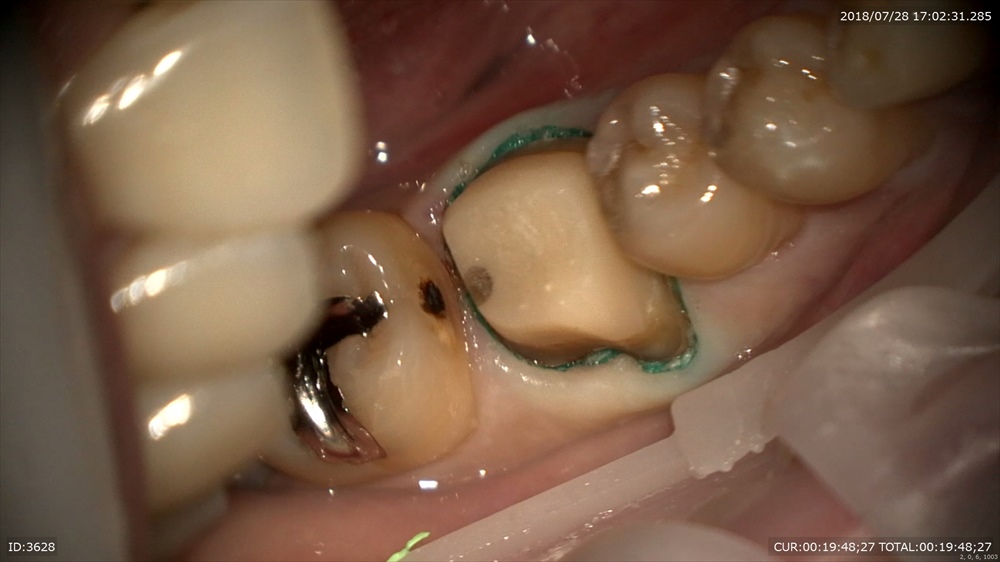

今日の患者さん。この方は他院の根管治療後腫れて治らず今年の年始にいらして頂きました。

歯科ドックの結果

歯周病治療、根管治療、土台、被せ物のやり直しが必要でした。

細かく根管治療

手間ヒマかけて

23倍でバイオフィルムを取り

土台をたて

仮歯で半年様子見

初診の腫れも消え症状もなく、患者さん

「抜歯しなくて良いのですね」

と喜んでいました。

歯周病治療後型取りをして

本日セット 技工士間中先生

少しの段差もありません、

このように重症の虫歯でも抜歯せずに治療ができます。ただし、